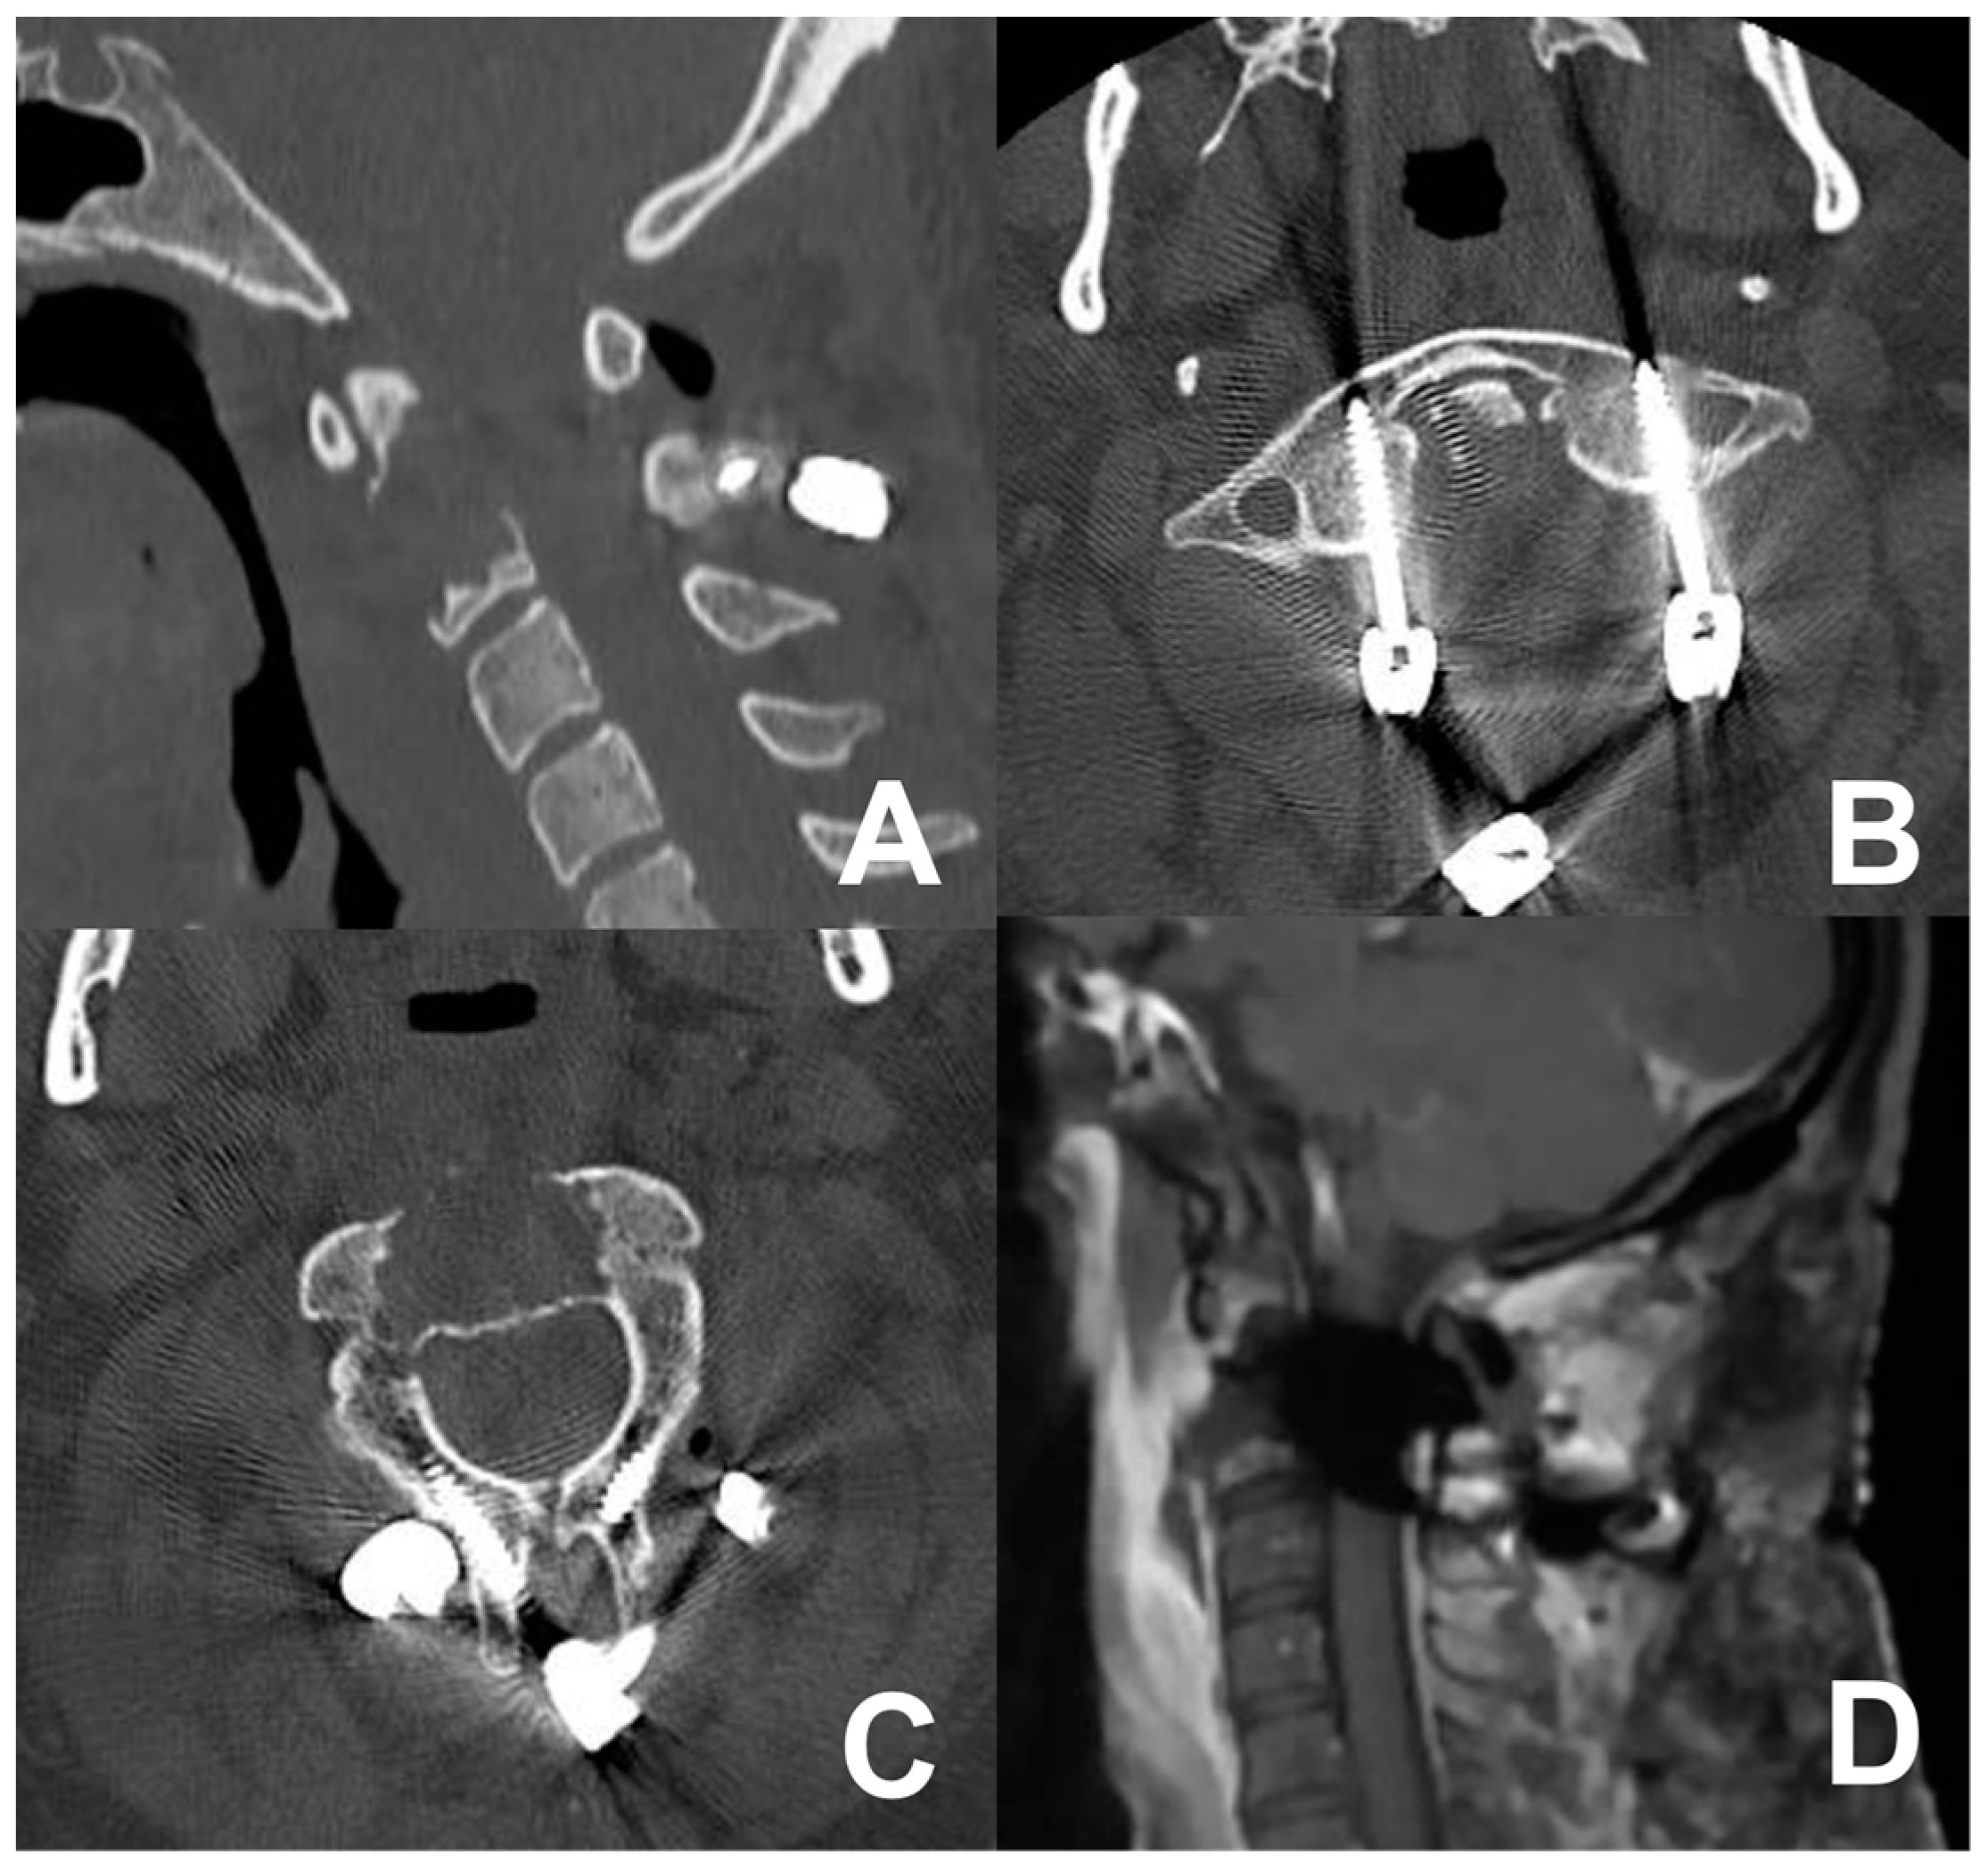

Figure 4.

Cervical MRI (A,B) and CT scan (C,D) showing the osteolytic lesion of the C2 vertebral body.

Figure 5.

Postoperative CT scan (A–C) and MRI (D) showing the extent of bone removal, tumor resection, and posterior fixation.